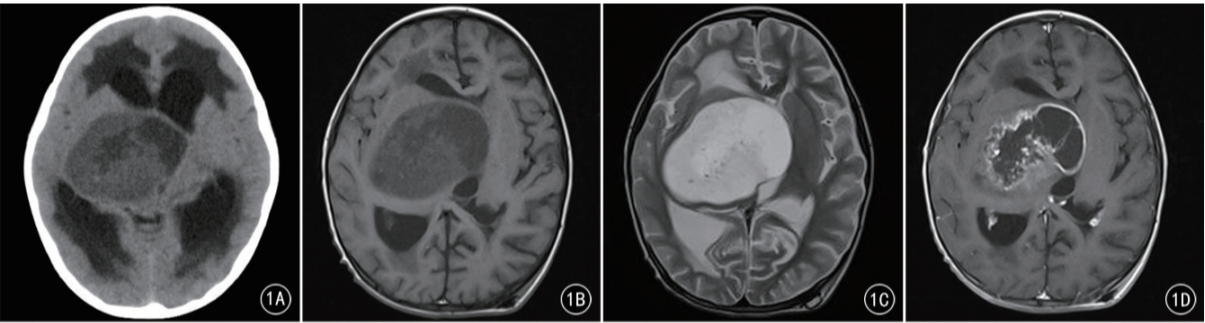

4d73fbf94bb490817626225a71f90e68.png

女,38个月,视交叉-下丘脑-右侧基底节区PMA(WHO Ⅱ级)

A.CT平扫示囊实性肿瘤,继发脑积水、间质性脑水肿,肿瘤实性部分为低密度

B.T1WI示肿瘤的实性部分为低信号

C.T2WI示肿瘤的实性部分为高信号,肿瘤边缘清楚,未见瘤周水肿

D.横断位增强扫描示肿瘤囊性部分的边缘早期即明显强化,呈“花环”样改变,囊变区较大且呈偏心性改变,而肿瘤的实性部分强化较弱,相对延缓

E.矢状位增强扫描后期示肿瘤囊性部分的边缘强化仍然明显,而肿瘤的实性部分呈渐进性强化,后期强化逐渐明显

F.组织学检查显示肿瘤组织基质黏液变明显,瘤细胞多为单极或双极细胞样围绕血管呈放射状排列或呈假菊形团样改变(HE × 200)